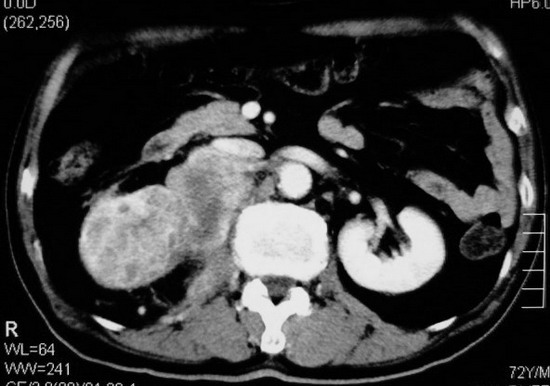

以下是引用杀毒软件在2008-11-17 19:15:00的发言:[br]考虑------右肾癌合并肾静脉---同侧肾上腺受侵可能性大

以下是引用zjzjr在2008-11-17 20:45:00的发言:[br]考虑------右肾癌合并肾静脉---同侧肾上腺受侵可能性大及腹膜后淋巴结转移.